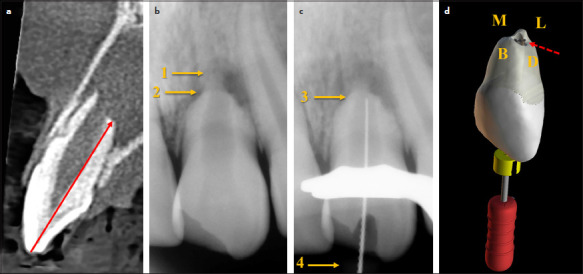

This research assessed the interobserver agreement and precision of the tactile method (TM) during orthograde exploration of the apical terminal portion of permanent teeth with necrotic pulps and open apices. Nine non-vital teeth with incomplete root development from nine patients were included. Two observers analyzed preoperative cone beam computed tomography (CBCT) images to determine the distance between the incisal reference point and the apical terminal portion at four apical measurement points: buccal, lingual, distal, and mesial. The shortest of these points was considered the tomographic working length (TWL) and was used as control group. Subsequently, endodontic access and light chemo-mechanical brushing of the main canals were performed, followed by radiographic working length (RWL) establishment. Two different operators applied the TM using a #25 manual K-file (Dentsply Maillefer, Ballaigues, Switzerland) pre-curved in the tip at a 90° angle. The same four apical measurement points were explored, and the tactile method working length (TMWL) was determined. Interobserver agreement was assessed using Bland-Altman method. Wilcoxon signed-rank test and Student's t-test were used to analyze the correlation between methods (p≤0.05). The measurements conducted for TM and TWL showed a high level of agreement (0.486 and -0.144 mm, respectively). Compared with the control group (TWL) and TMWL, the RWL showed no significant correlation (<0.001 and 0.0068, respectively). TM demonstrated a reliable level of inter-observer agreement and could prove valuable when treating permanent teeth exhibiting non-vital pulps and open apices, especially in cases with radiographic evidence of external inflammatory apical resorption. (EEJ-2024-11-187).